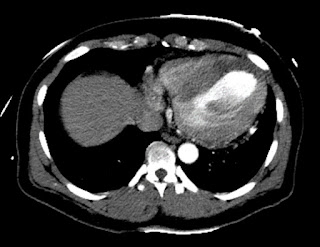

Поэтому была сделана КТ, которая, конечно, показала нормальную аорту. Но она также показала огромную область тотальной ишемии в области ПМЖВ:

КТ показывает инфаркт

КТ с контрастом, что увеличивает плотность (которая выглядит более белой). Миокард, в котором нет кровотока, не получает контраста, и поэтому выглядит более темным.

Посмотрите на темную область в перегородке и верхушке, выделенную белым кругом: